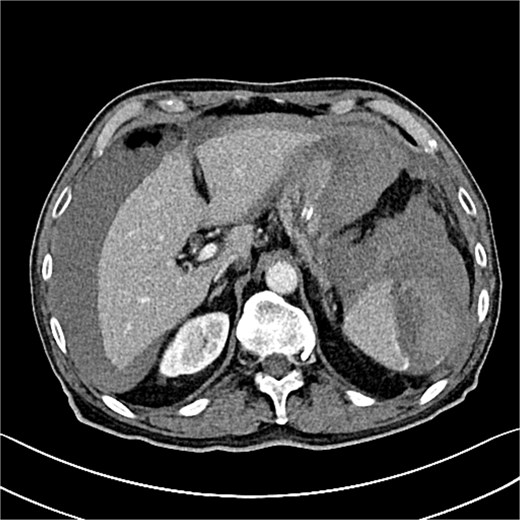

![Grade III splenic injury with intraparenchymal hematoma larger than 5 cm [5].](https://oupdevcdn.silverchair-staging.com/oup/backfile/Content_public/Journal/jscr/2025/5/10.1093_jscr_rjaf313/2/m_rjaf313f2.jpeg?Expires=1777615725&Signature=gPfa59YPySaNQOE-jveOdRelIqp5~U9w7R4eWbOoaiObzW4QFpM7wXYkJahBghm~uLwrUiqoGefjtCiWmk5p9CTK5tKrtgiTVfiJ5cG5MV0nhZpCkT2rNwnJun2ZQk2R4cu-ttMg1dq1MUtK7BiMVBGKtQhM3vasGvFYNNSQHGqCcZzsUF~TrUKaiJNpw0SI6MmPBKZobo8CCt8N4qbJQYxaqV5Pei8g8nzc1zwNH8uG315evIGWPh-cRTvm~h1EmQUF1a6feNw2vTcBG8nSQLWSDHdZ~Yxb8QeUF0IwCfnjYJbVJAkRWzxqd3Tct6T-pdPIhNJ7S5qoNIKJ~Vq~uA__&Key-Pair-Id=APKAIYYTVHKX7JZB5EAA)

Grade III splenic injury with intraparenchymal hematoma larger than 5 cm [5].